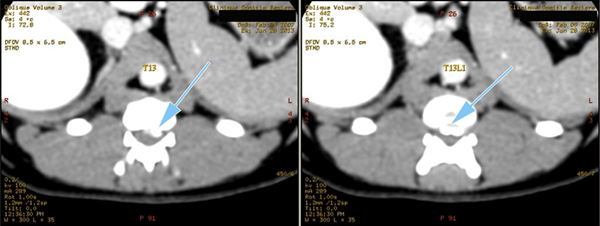

Coupes axiales

Scanner d'une Hernie discale T13L1 extrusive chez un chien reformatages sagittal et coronale